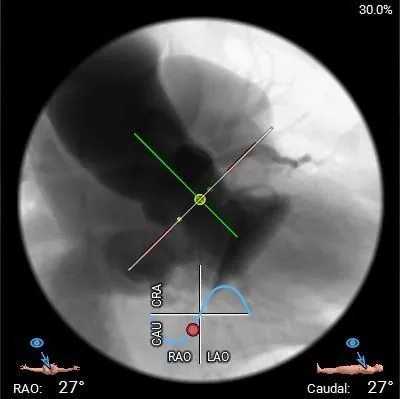

工作体位

右窦中心

左右重合

左冠切线

瓣膜选择:ScienCrown TAVTF27mm 0位定位释放;

根部造影